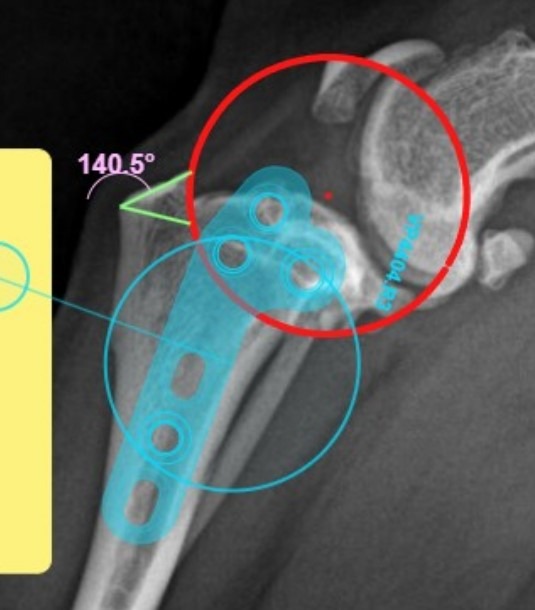

미래동물의료센터는 수술 전 시뮬레이션 프로그램을 통해 사용할 스크류와 플레이트의 크기,

경골 절골 후 각도 및 거리 변화를 미리 계산한 뒤 수술을 진행했습니다.

환자 수술 사진/ 출처: 미래동물의료센터